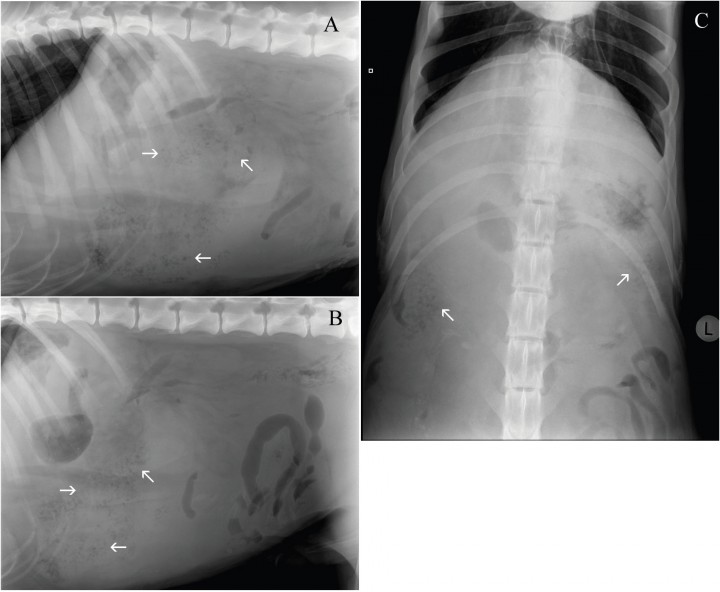

Se presentó en la consulta un perro macho mestizo entero de 5 años de edad y 57 Kg de peso con anorexia, letargia y taquipnea de 3 días de evolución. En la exploración física, se evidenció abdomen distendido y doloroso, taquipnea, mucosas pálidas, tiempo de relleno capilar disminuido, deshidratación y taquicardia. Las alteraciones observadas en la analítica sanguínea fueron anemia (32%, valor de referencia 37-55%) y leucocitosis (22,13 x103/mm3, valor de referencia 5,5-16.9 x103/mm3) con desviación a la izquierda. En la bioquímica sérica se observó un aumento de la fosfatasa alcalina (234 UI/l, valor de referencia 30-120 UI/l), amilasa (2246 UI/l, valor de referencia 250-1300 UI/l) y urea (128 mg/dl, valor de referencia 43-108 mg/dl). Se realizaron radiografías de la cavidad abdominal (Fig. 1).

<p>Proyección lateral derecha de la zona craneal (A) y caudal (B) y ventrodorsal (C) del abdomen de un perro que se presenta con anorexia, letargia y taquipnea de 3 días de evolución.</p>

Proyección lateral derecha de la zona craneal (A) y caudal (B) y ventrodorsal (C) del abdomen de un perro que se presenta con anorexia, letargia y taquipnea de 3 días de evolución.

Se observa pérdida de visualización de serosas y una masa localizada en el abdomen craneoventral tanto en el lado derecho como en el izquierdo, con bordes mal definidos, de opacidad tejido blando conteniendo en su interior múltiples focos radiotransparentes irregulares de pequeño tamaño. Las asas de intestino delgado se visualizan desplazadas caudalmente (Fig. 2).

<p>Mismas imágenes que la Fig 1. Se observa pérdida de visualización de serosas y una masa localizada en el abdomen craneoventral (A y B), tanto en el lado derecho como izquierdo (C), con bordes mal definidos, de opacidad tejido blando conteniendo en su interior múltiples focos radiotransparentes irregulares de pequeño tamaño (flechas) desplazando las asas intestinales caudalmente.</p>

Mismas imágenes que la Fig 1. Se observa pérdida de visualización de serosas y una masa localizada en el abdomen craneoventral (A y B), tanto en el lado derecho como izquierdo (C), con bordes mal definidos, de opacidad tejido blando conteniendo en su interior múltiples focos radiotransparentes irregulares de pequeño tamaño (flechas) desplazando las asas intestinales caudalmente.

¿Cuáles son los diagnósticos diferenciales con estos signos radiológicos?

Una masa localizada en el abdomen craneoventral y en ambos lados, lo más probable es que sea una masa esplénica. Los diagnósticos diferenciales incluyen torsión esplénica, esplenitis y neoplasia. Las áreas radiolúcidas observadas podrían deberse, o bien a una torsión esplénica enfisematosa, o a una infección con bacterias formadoras gas. La pérdida de visualización de serosas sería compatible con líquido libre. En base a todos los hallazgos radiográficos se realizó un diagnóstico presuntivo de torsión esplénica enfisematosa o infección con bacterias productoras de gas.